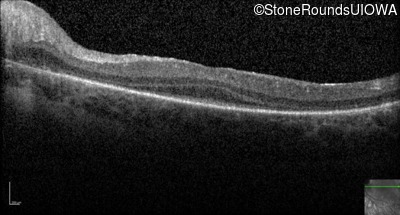

Optical Coherence Tomography - Left -

Light Perception

Exemplar

Expanded OCT Stack

×